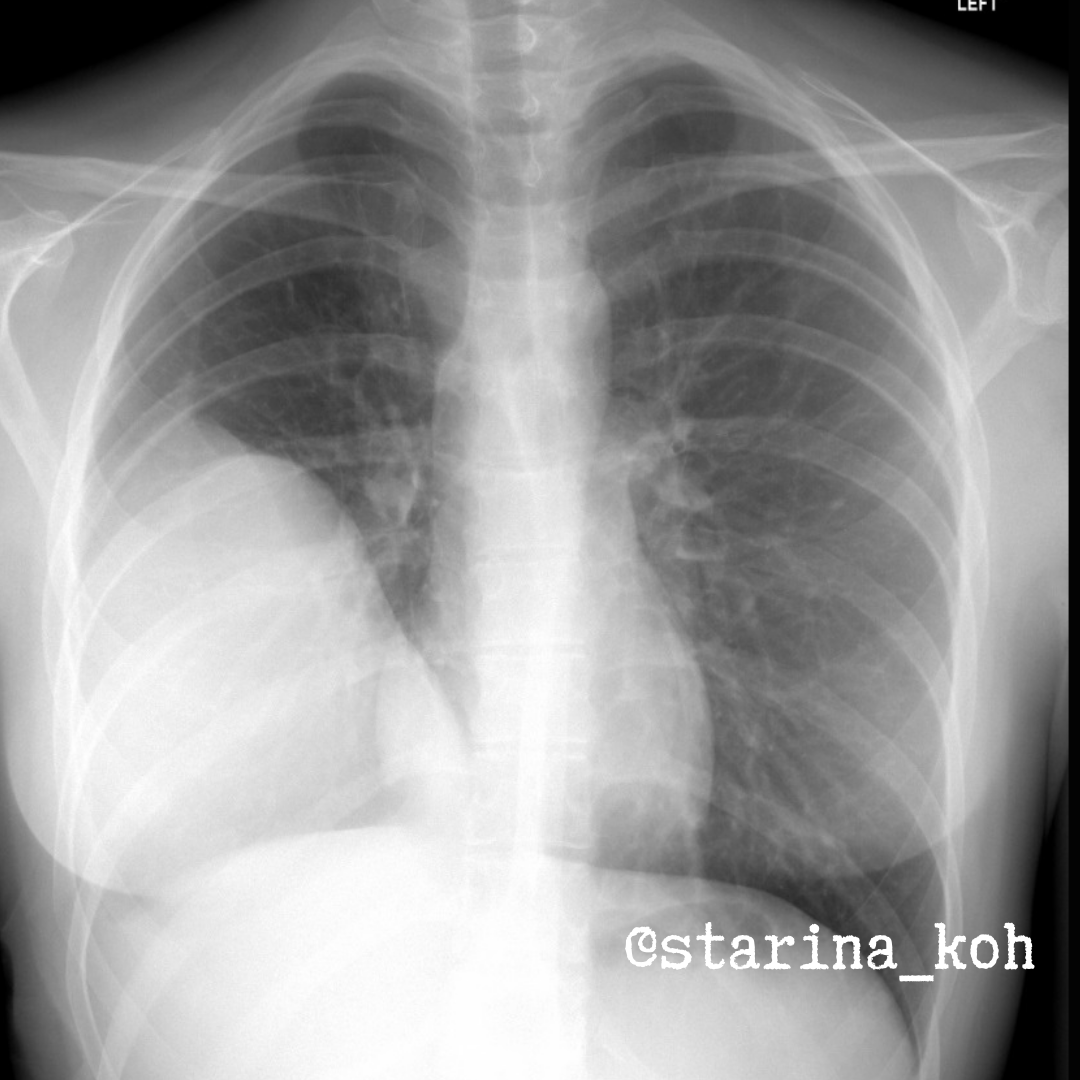

Молодая девушка 25 лет стала обращать внимание, что примерно во второй половине 2022 г. у нее появился дискомфорт, тяжесть в грудной клетке, а периодически и болевые ощущения справа, особенно при дыхании. В рамках проф. осмотра выполнили ФЛГ, где выявили крупное затемнение в проекции правого лёгочного поля (похоже и на осумкованный плевральный выпот и на образование). Врач в поликлинике в т.ч. рекомендовал исключить туберкулез (данные в дальнейшем не получены).

Была выполнена КТ ОГК, где подозревали образование либо эхинококковую кисту. После проведения контрастного усиления идея про эхинококкоз отпала сама собой т.к. образование имело преимущественно солидное (плотное) строение. Была выполнена трансторакальная биопсия, в материале получены опухолевые клетки, подозрительные на мезотеолиому. Однако, врачи усомнились в таком диагнозе, т.к. опухоль имела преимущественно крупноузловое строение и не распространялась диффузно как мезотелиома. Был выполнен пересмотр препаратов еще в одном онкологическом учреждении, где дополнительно провели ИГХ-анализ и вынесли заключение о бифазной синовиальной саркоме (бифазные саркомы - сочетающие в своем строении два различных тканевых компонента и фенотипа).

По данным КТ в правом гемитораксе - крупная опухолевая масса в средних и нижних отделах, на большем протяжении прилежит к грудной стенке/плевре, без четких границ с тканями, имеет солидное строение (контрастируется) с кистозными включениями, что особенно хорошо видно по данным МРТ.

Прилежащие отделы лёгкого компримированы, в плевральной полости - небольшое количество жидкости. При поступлении в онкологический стационар жалобы прежние, Sat02 - 96%, в анализах крови без отклонений. Выполнена операция - удаление опухоли (около 20 см), при котором обнаружена инвазия в нижнюю долю лёгкого и межреберные мышцы (доля легкого удалена, мышцы иссечены в пределах здоровых тканей), инвазия в диафрагму и структуры корня лёгкого не выявлена. Морфологически опухоль представлена бугристым узлом, серовато-желтым на разрезе, с кровоизлияниями, при повторной ИГХ - синовиальная саркома GIII. Пациентка выписана для подбора химиотерапии. По данным КТ с контрастированием, опухоль не характерна для мезотелиомы, а вот дифференцировать с солитарной фиброзной опухолью плевры возможно т.к. даже макроскопически эти опухоли похожи друг на друга.